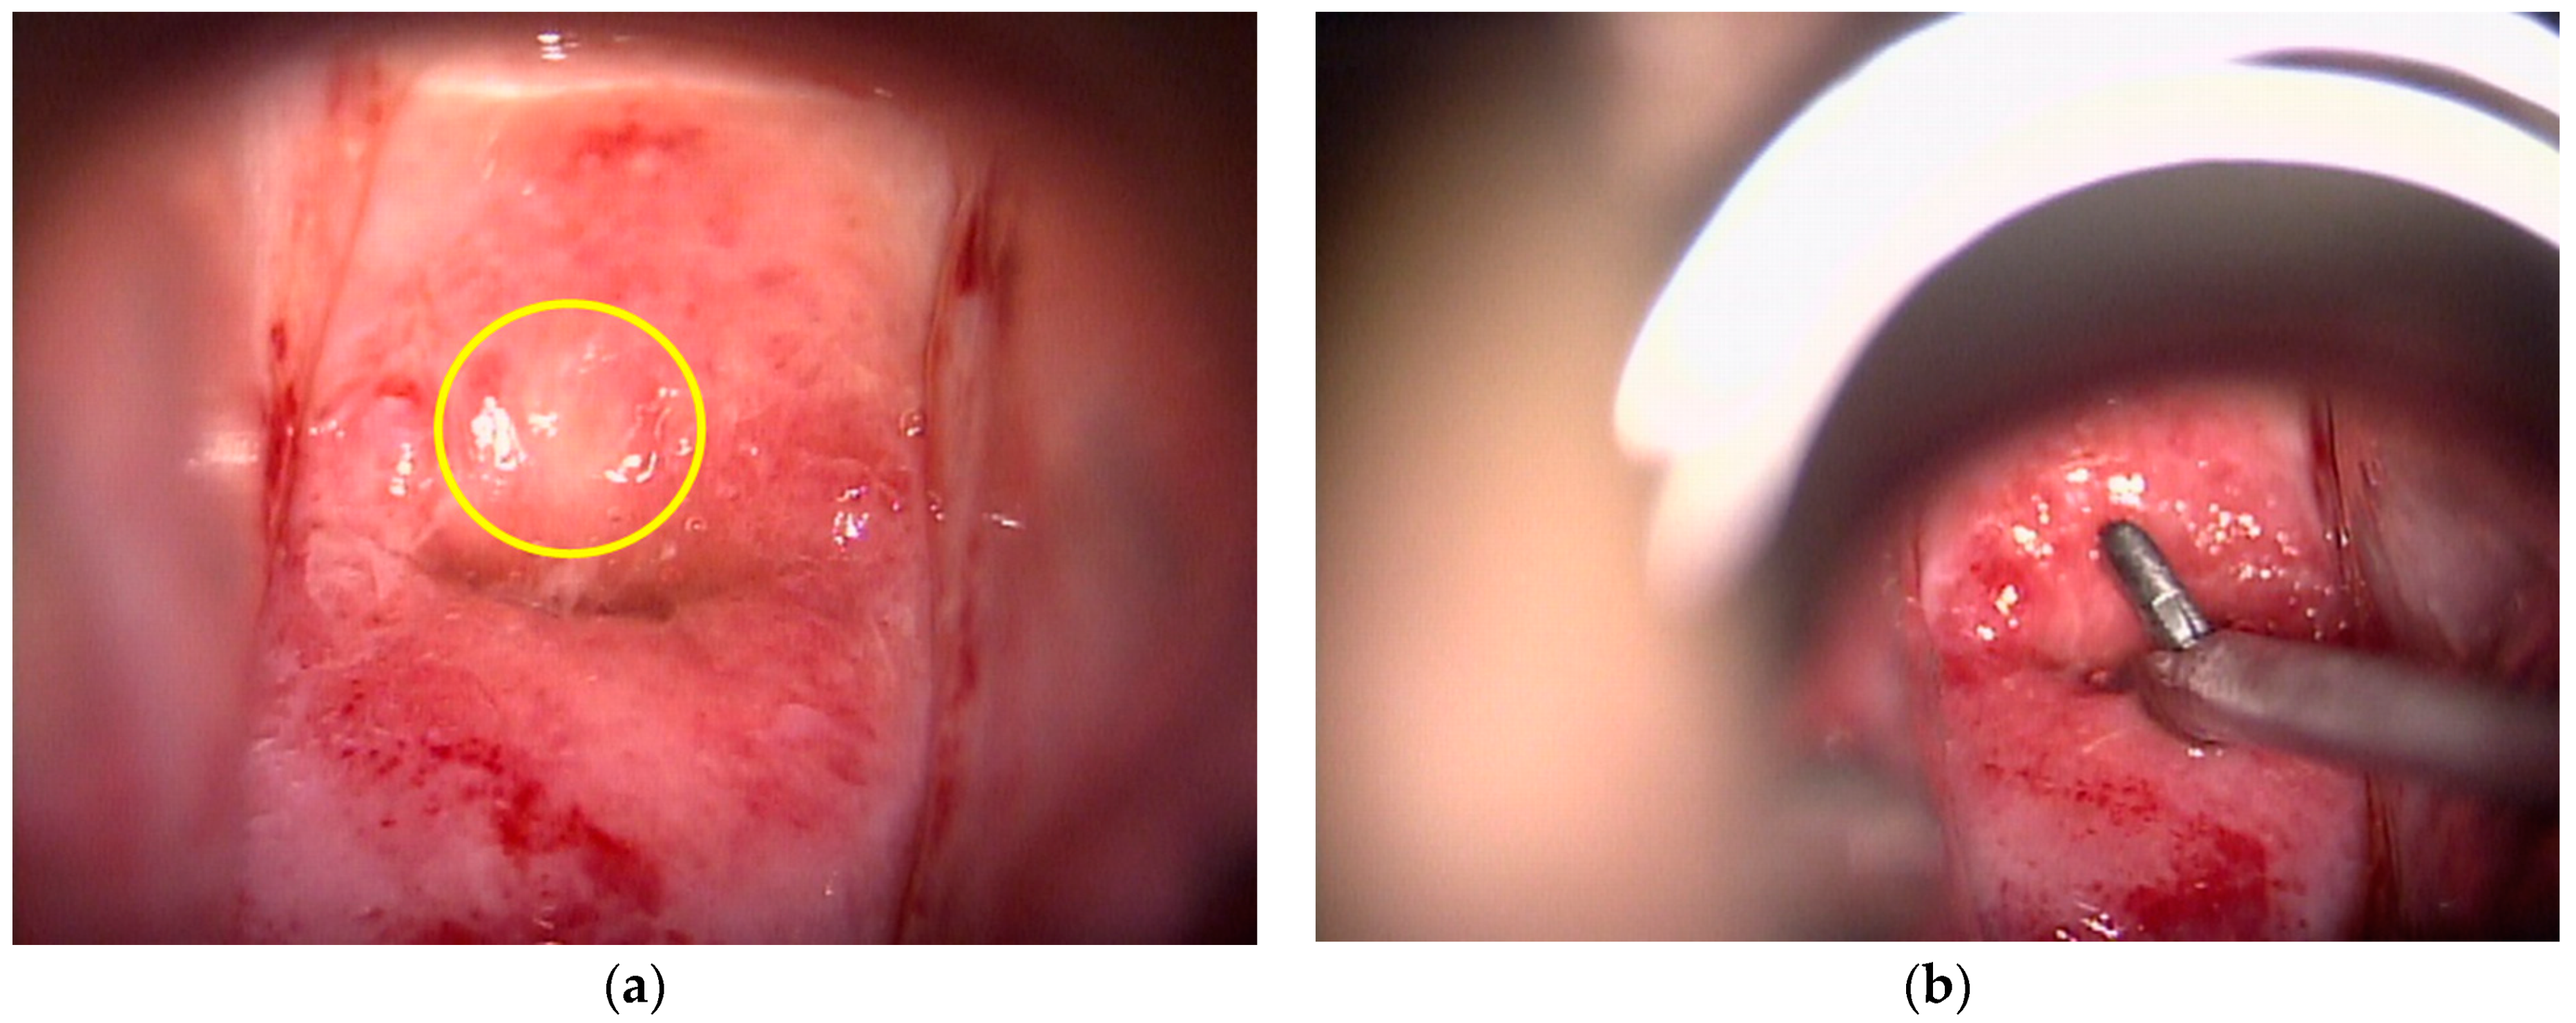

2.2. Colposcopic Procedure

2.3. Endoscopic Procedure